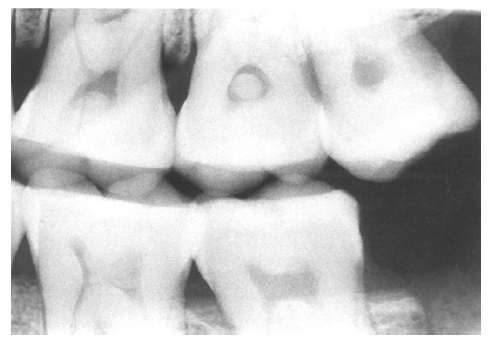

Figure 4 - Recurrent Caries

Figure 4

In Figure 4, recurrent caries appears at the mesial of tooth #3 and #4, and the distal of tooth #28. Also, note areas of interproximal caries on teeth #5-6.

Recurrent caries is the condition in which carious lesions develop or extend along the margins of existing restorations. A diligent search for recurrent caries should be made whenever radiographic images detect:

• interproximal restoration overhangs

• open margins on restorations

• restorations which appear to end short of preparation margins; or

• restorations which appear unusually shallow as judged by the thickness of the restorative material.

Radiographically, recurrent caries presents as radiolucent lines that extend inward from the tooth surface along a restoration or as radiolucent zones, which appear to lie completely beneath the restoration without any observable communication with the tooth surface. As mentioned previously, the junction of a restored tooth and the restorative material should appear sharp and distinct, and, as a rule, recurrent caries should be suspected whenever radiolucencies are present between the tooth and the restoration.